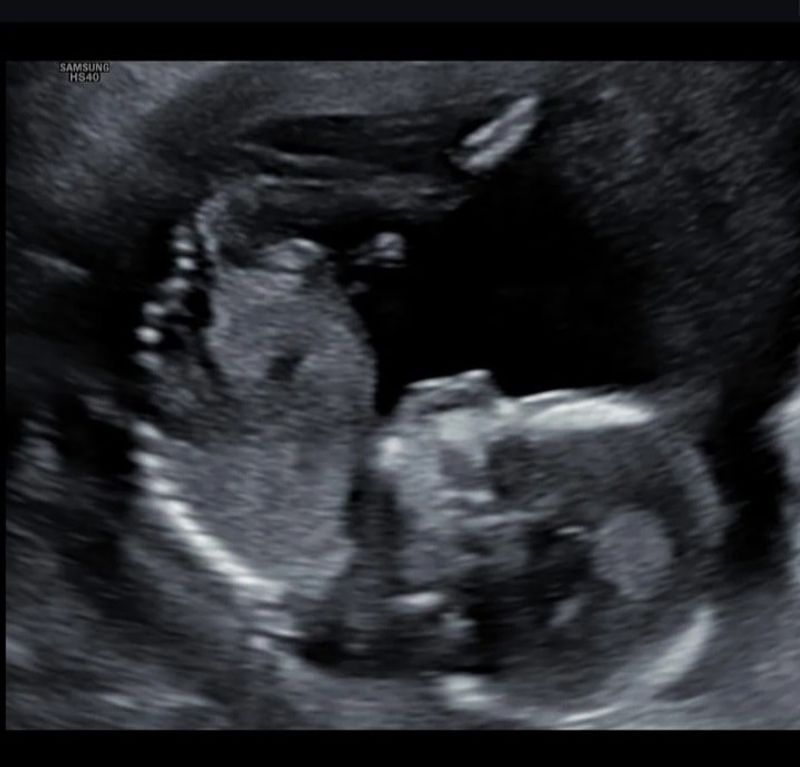

Ook wij kregen een wonder

De baby’s om ons heen werden peuters en ook onze eigen dochter werd steeds groter en wijzer, zonder broertje of zusje. Haar vriendjes en vriendinnetjes werden grote broer of zus, en zij niet. Wij zagen het verdriet bij haar en dit brak mijn hart. Ik faalde niet alleen als vrouw, maar ook als moeder. Ik heb mezelf gek gemaakt met allemaal gedachten dat ik het niet meer waard was. “Helemaal stoppen? Wanneer stop ik met deze medische mallemolen? Hoe ver wil ik gaan?”, vroeg ik me hardop af. Toch bleef ik mij verschuilen achter een vrolijk masker en de strippen paracetamol. Maar dan ineens, vier jaar na die ene beslissing, 48 zwangerschapstesten verder, voor mijn gevoel wel 110 injectiespuiten en 10 dozen “poezenbollen” (die smerige progesteron capsules) en 2 hele dagen overtijd na een verse terugplaatsing van IVF2, had ik ineens een positieve test in handen. Inmiddels ben ik 16 weken zwanger van Elena haar broertje en ons lang verwachte tweede kind. Toen ik bijna niet meer in wonderen geloofde, was daar dan ook voor ons dit kleine grote wonder.